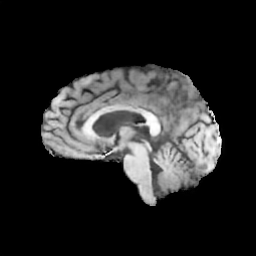

The results presented in Table 1 and 2 show our proposed method’s performance on unconditional 3D brain MR and chest CT image generation. Our proposed approach not only outperforms most comparing methods in FID and MS-SSIM metrics, it also has the lowest inference GPU memory footprint at a resolution of and was the only diffusion-based method that could be trained at a resolution of . Operating in the wavelet domain and profiting from the reduced spatial dimension also results in a relatively short inference time of / at the respective resolutions. Compared to the results presented in [23], we did not find that incorporating wavelet information into the network’s feature space (WavU-Net) increased the model’s performance. Qualitative results of our proposed method (WDM) are shown in Fig. 2 and 3. A qualitative comparison of samples produced by all evaluated methods can be found in the Supplementary Material.